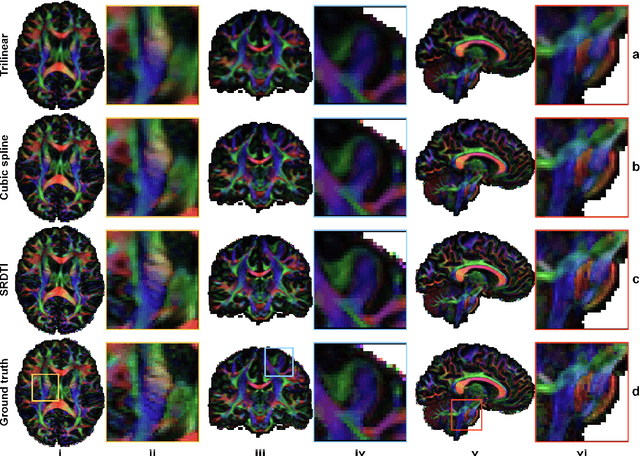

Abstract:High-resolution diffusion tensor imaging (DTI) is beneficial for probing tissue microstructure in fine neuroanatomical structures, but long scan times and limited signal-to-noise ratio pose significant barriers to acquiring DTI at sub-millimeter resolution. To address this challenge, we propose a deep learning-based super-resolution method entitled "SRDTI" to synthesize high-resolution diffusion-weighted images (DWIs) from low-resolution DWIs. SRDTI employs a deep convolutional neural network (CNN), residual learning and multi-contrast imaging, and generates high-quality results with rich textural details and microstructural information, which are more similar to high-resolution ground truth than those from trilinear and cubic spline interpolation.